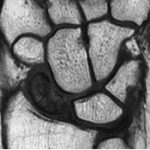

La maladie de Kienbock se définit comme une nécrose aseptique du semi-lunaire (un os appartenant à la première rangée du carpe) sans notion de traumatisme.

Les radiographies standards du poignet de face et de profil peuvent être normales à un stade de début : il faut en cas de doute diagnostique, pratiquer une IRM ou un scanner ; ces examens vont montrer une différence de contraste ou des altérations osseuses en faveur d’une nécrose débutante sur le semi-lunaire.